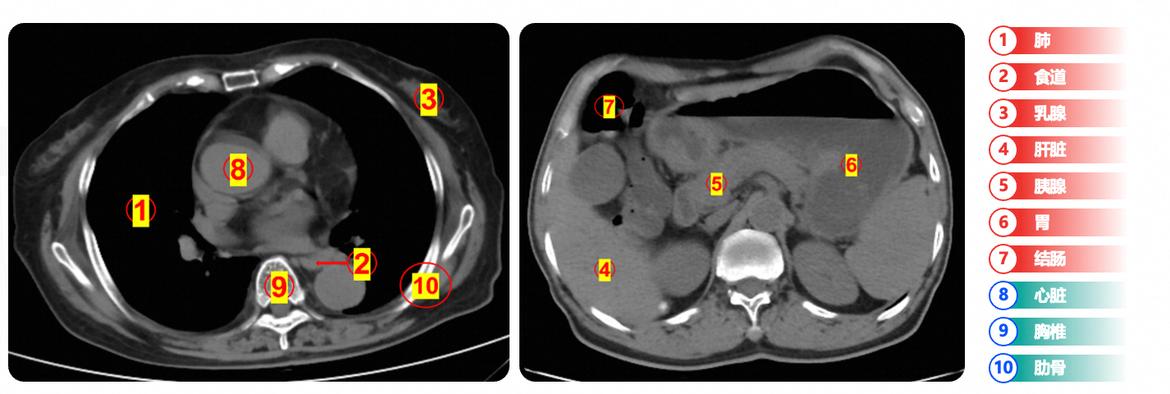

老美估计也没想到,自家的百年巨头企业转身投入中国怀抱,现实真的太残酷! 近期上海进博会上传出的一则消息挺耐人寻味,在美国有着百年历史的巨头企业GE医疗宣布和阿里达摩院签约,有意引入阿里达摩院首创的“一扫多查”医疗AI技术。 两者的合作可没有表面那么简单,背后释放的信号,很多人肯定都没有看明白。 或许很多人不知道,GE医疗是美国一家拥有120多年历史的百年企业,同时和飞利浦、西门子并称为医疗设备三巨头。 在整个医疗设备领域,那绝对是“泰山北斗”般的存在,影响力不可谓不大。但即使是这样的一家企业,同样在投向中国,和阿里达成AI合作。 这背后就很好的说明了两件事。 第一,AI时代下,百年企业想要继续生存,继续保持优势也得进行转型才行,这是一个现实的问题。 毕竟就算GE医疗的CT机能够拍摄出再高清的医疗影像也没用。因为在阿里医疗AI的助力之下,如今在中国,咱们已经可以实现在普通平扫CT中,用AI技术去识别医生肉眼难以发现的细微病灶,对包括胰腺癌、胃癌在内的多种癌症进行早期筛查。 这可不是我瞎说,早在两年前,阿里达摩院就发布了胰腺癌筛查AI模型,成功在2万多名患者中通过平扫CT+AI的方式,发现了30多例临床漏诊病变,其中2例早期胰腺癌病患还完成了手术治愈。 很明显,AI时代的来临也代表了市场的重新洗牌,而在这种情况下,作为百年巨头的GE想要不被淘汰,最好的解法就是进行转型,拥抱AI,抱住中国AI的大腿。 第二,中国AI正在加速走出国门,这一次GE医疗和阿里医疗AI的合作,背后其实也透露了另一个问题。 GE医疗是美国的巨头企业,选择技术合作时,选中的却是阿里医疗AI,并且不只是它,在更早之前,像苹果、宝马、SAP、英伟达等等,他们都曾和阿里AI达成过合作。 可以这么说,中国AI技术实力强,性价比更高,正在成为全球众多企业的新选择,成为全球AI技术的应用一极。